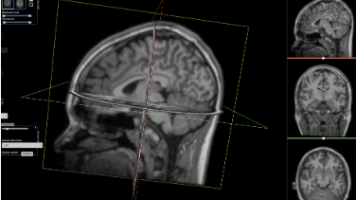

本文从软件工程视角解析3D医疗影像AI的数据处理流程。首先通过HU值裁剪和归一化完成数据清洗,将CT值映射到[0,1]区间;然后采用96×96×96子体积分块策略解决显存限制;接着引入旋转、强度偏移等数据增强技术提升模型鲁棒性;最后采用AdamW优化器以0.0001学习率进行40000次迭代优化。整个流程展示了深度学习系统与传统软件开发在数据标准化、内存管理和鲁棒性设计上的共通之处。

本文介绍了一种结合Transformer与nnU-Net的3D医学影像分割新方法nnFormer。该方法通过Transformer的全局注意力机制弥补传统CNN的局部视野局限,同时利用nnU-Net的自动化配置简化训练流程。实验表明,nnFormer在脑肿瘤、多器官分割等任务上性能优异,特别是通过模型集成策略nnAvg进一步提升了分割精度。该方法展现了Transformer在医学影像处理中的优势,